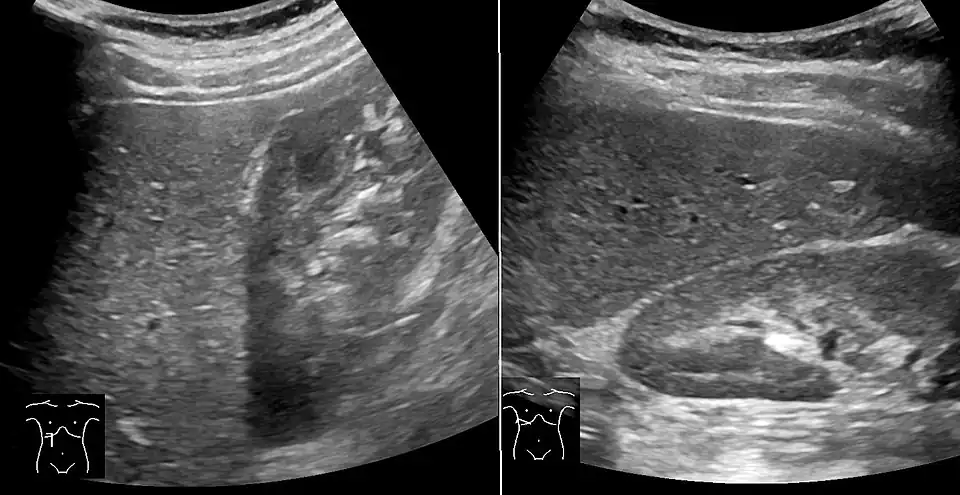

Abdominal ultrasonography of focal steatosis. It is distinguished from a tumor by not compressing the hepatic vein.